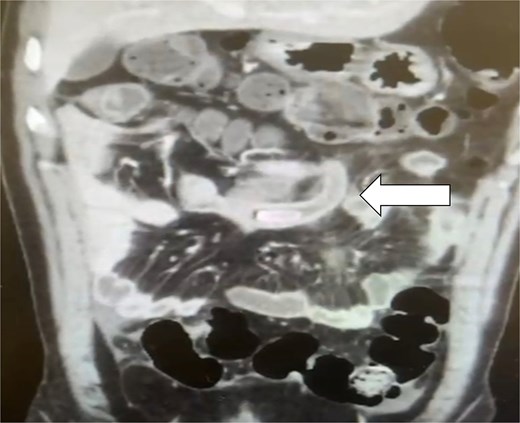

An X-ray of the abdomen showed mild distention with a few air-fluid levels; the chest X-ray was normal. The patient was admitted immediately, and a computed tomography (CT) scan was ordered. The CT scan revealed IM, indicated by the abnormal positioning of the mesenteric vessels, with the superior mesenteric vein located to the right of the superior mesenteric artery. The duodenal-jejunal junction was abnormally positioned in the right hypochondrium, while the cecum and terminal ileum were located in the mid-upper abdomen. Additionally, a dilated appendix measuring 1.2 cm, with a large appendicolith and thickened wall, was identified in the mid-upper abdomen in a sub-caecal position (see Fig. 1). The patient consented to a laparoscopic appendectomy.

CT scan coronal view demonstrating the appendix with appendicolith at the mid-abdomen due to incomplete malrotation.